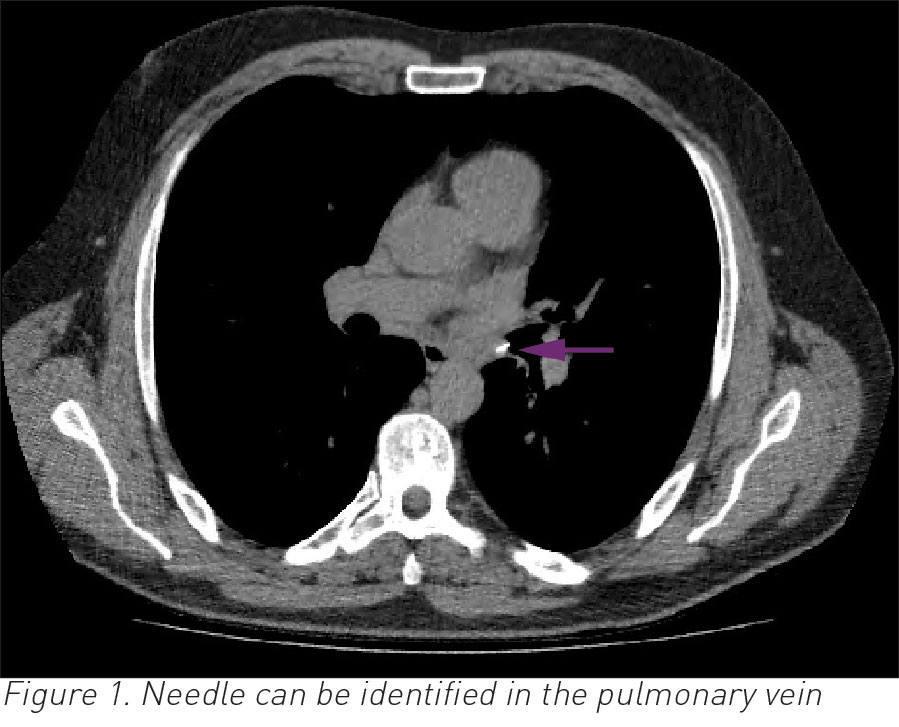

A CT thorax was performed to further evaluate for cause of haemoptysis. Imaging showed a needle in the left main bronchus entering the main pulmonary vein (see Figures 1 and 2).